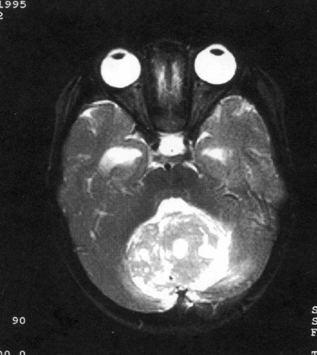

病历摘要:??患儿男性,11岁。半年前开始出现行走不稳,常无故跌倒。半月前出现发作性剧烈头痛,伴恶心呕吐。体检:T36℃,P100次/分,R22次/分,B...

问题 病历摘要:??患儿男性,11岁。半年前开始出现行走不稳,常无故跌倒。半月前出现发作性剧烈头痛,伴恶心呕吐。体检:T36℃,P100次/分,R22次/分,BP100/60mmHg,神清,言语较缓慢,双眼外展约不及边,双眼侧视时有小幅度水平眼震。四肢肌力正常,右上肢肌张力较低,坐位姿势不稳,常不自主摇晃,双上肢指鼻不准,行走蹒跚步态,足距扩大,身前倾。 关于手术的描述,哪些是正确的?提示:拟手术治疗

选项 A.枕下后正中开颅 B.打开枕骨大孔后缘及环椎后弓 C.小脑蚓部横行切开 D.阻断一侧小脑后下动脉不会引起明显并发症 E.即使肿瘤侵入第四脑室底,也要争取全切肿瘤 F.术中至少要打通脑脊液循环通路 G.必要时可行Torkildson分流术 H.硬膜敞开,但要严密缝合肌层及头皮

答案 ABFGH